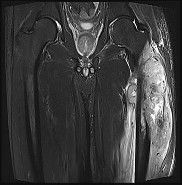

Figures 5a and 5b are the radiographs of a 74-year-old man with poorly differentiated squamous cell carcinoma of the lung. He has had an uneventful recovery after undergoing a wedge resection of his left upper lobe 6 months ago. He is experiencing left lateral knee pain, and a whole-body positron emission tomography/CT scan shows no avid area other than the lateral left distal femur. This patient has needed to use a wheelchair for 3 weeks because of his pain. You discuss these treatment options: aggressive curettage, local adjuvant treatment, cementation, and prophylactic fixation vs distal femoral resection and megaprosthesis total knee arthroplasty reconstruction. You should tell him that

Distal femoral megaprosthetic reconstruction after tumor resection is a reliable oncologic procedure, but 5-year implant survival is as low as 74% with an approximate 8% deep infection rate. The amputation rate is as high as 8% because of infection or recurrence, and there is an overall 18% revision rate. More than 10% of distal femoral megaprosthetic reconstructions are performed to address metastatic disease.

Fixation failure and infection may occur with either procedure. Radiation may not be recommended after a megaprosthesis reconstruction unless margins are not free of tumor. Either operation may be equally successful in returning patients to functional activities. Overall disease-free survival is related to the aggressiveness of the tumor and not the type of reconstruction performed.